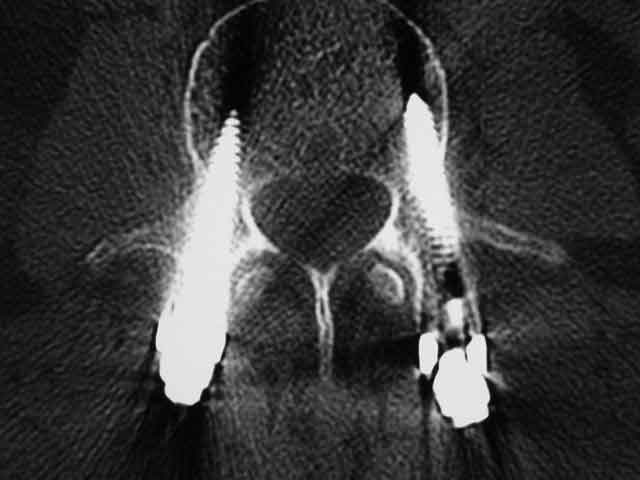

Knochenschrauben im Wirbel: Mit Computernavigation wird die Stabilisierung durchgeführt und gibt dem Patienten maximale Sicherheit.